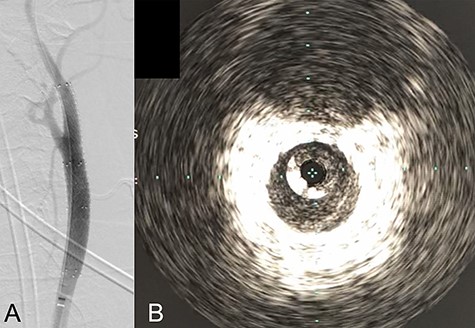

We performed CAS and started dual antiplatelet therapy 27 days after stroke onset to prevent further dissection and cerebral infarction recurrence. The dissection started 1.5-cm below the carotid bifurcation (Fig. 3A). An 8 fr guiding catheter (FlowGate2 Balloon Guide Catheter, Stryker, Fremont, CA, USA) was positioned at the proximal portion of the left CCA with a micro-guidewire (ASAHI CHIKAI Black, Asahi-Intecc, Nagoya, Aichi, Japan) crossing the dissected lesion. A distal protection device (SpiderFx Embolic Protection Device, Medtronic, Minneapolis, MN, USA) was deployed at the petrous portion of the ICA. IVUS was first advanced into the petrous ICA, and vessel wall imaging was performed by slowly withdrawing the device. IVUS imaging confirmed the existence of the dissection’s pseudo-lumen starting 1-cm proximal to the carotid bifurcation (Fig. 3C). IVUS provided the ICA and CCA diameters, which helped decide the most suitable stent (Fig. 3B and C). To adequately cover the dissection lesion, we placed two opened cell stents (Protégé, Medtronic, Minneapolis, MN, USA); one was an 8–6-mm tapered model with a length of 40 mm to cover the lesion from the distal CCA end to the proximal portion of ICA. Another was a 10-mm straight model with a length of 40 mm covering the CCA. Post-dilation was performed SterlingTM Balloon Dilation Catheter (Boston Scientific, Natick, MA, USA) with 5 × 20 mm covering both stents’ edges. The final angiography showed successful treatment with a smooth intra-arterial lumen (Fig. 4A). IVUS imaging showed sufficient stent coverage of the entire dissection lesion. It also confirmed a good expansion of the stent to the dissection area’s arterial wall with no plaque protruding the stents (Fig. 4B).

Angiography after stent placement showed favorable patency of the carotid artery with a smooth intra-arterial lumen (A). IVUS performed after stenting confirmed an excellent expansion of the stent to the dissection lesion’s arterial wall with no plaque protruding the stents (B).

We would further like to note the usefulness of IVUS in this particular case. IVUS clearly visualized both the dissection’s entry point and the blood flow from true- to pseudo-lumen, the information of which is essential for treatment strategy planning. IVUS also provided helpful information to assess the stent’s coverage (Fig. 3). IVUS allowed us to predict the entire length of the arterial dissection before stent deployment [11]. Furthermore, IVUS provided important information for stent-size selection. Although the pseudo-lumen caused by the dissection made it difficult for us to precisely measure the true lumen diameter, IVUS allowed us to measure the diameter of the true lumen of the dissected artery, and we were able to select the appropriate stent for treatment. It also provided helpful information that proper stent apposition was established even after the stent deployment and post-balloon dilation, which indicated no additional angioplasty was necessary.